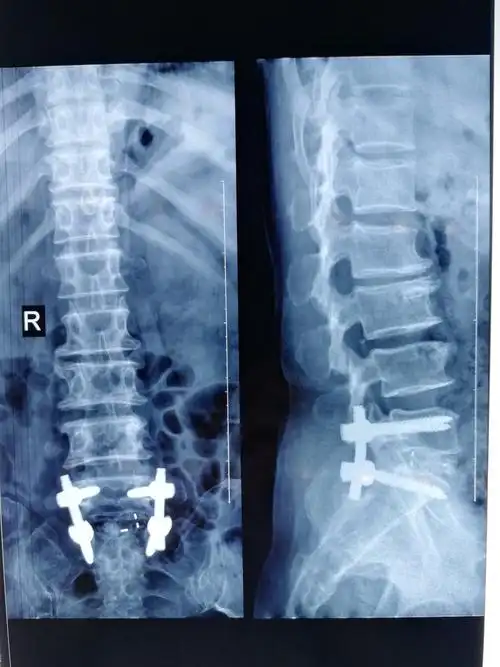

腰椎间孔镜治疗椎间盘突出1例

典型案例二:男,48岁,腰椎间盘突出.

腰椎间盘突出症